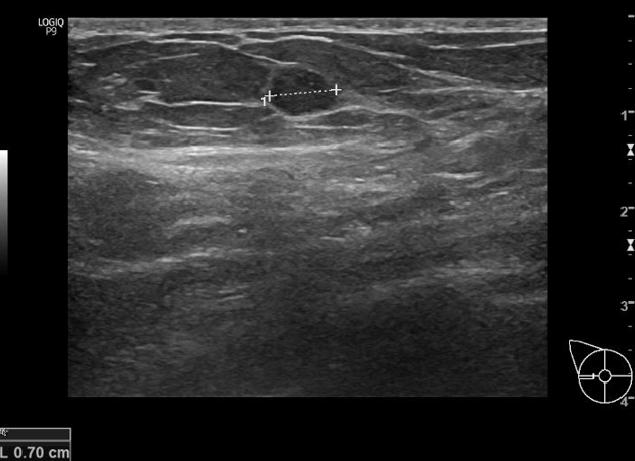

Термин «гипоэхогенный узел щитовидной железы» используется при трактовке данных, полученных в ходе УЗИ, – процедуры, базирующейся на принципе, что структуры разной плотности по-разному проводят ультразвуковые волны.

Такие новообразования имеют пониженную плотность по сравнению с другими тканями органа и выглядят на мониторе как темные пятна.

Их наличие – не основание для постановки диагноза, но повод для дальнейшего обследования. В зависимости от особенностей случая они могут быть как признаком заболевания, так и вариантом нормы.